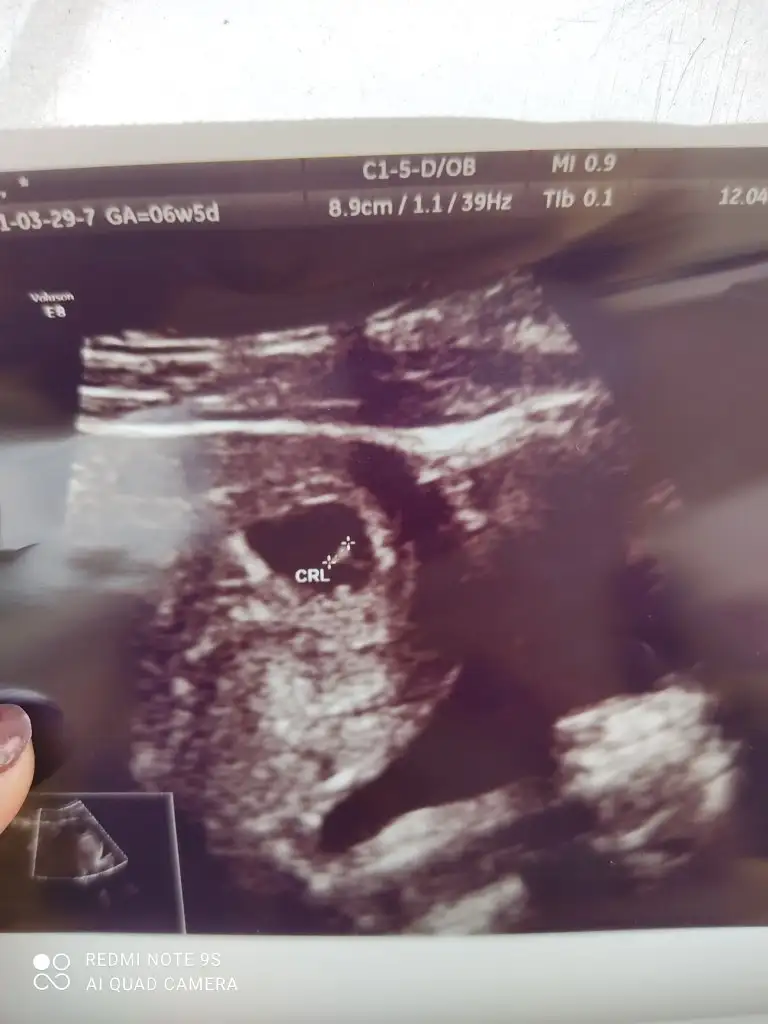

merhabalar benimkini de tahmin edebilir misiniz ?7+1 Eki Görüntüle 2820851

Bu arada karından çekimmerhabalar benimkini de tahmin edebilir misiniz ?7+1 Eki Görüntüle 2820851